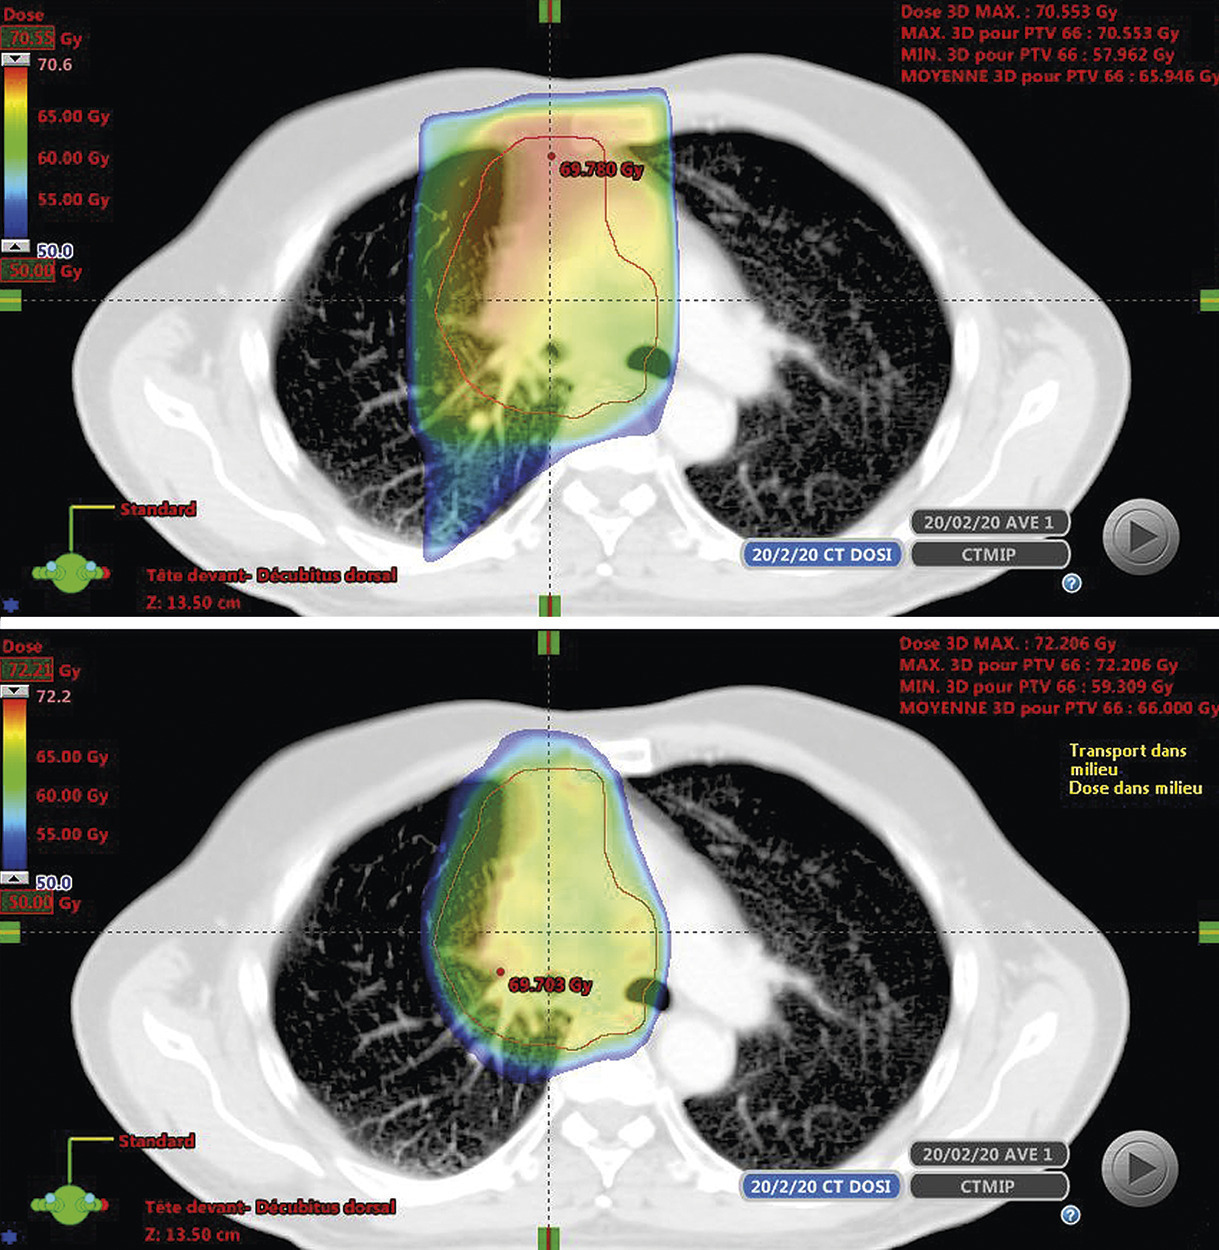

Il y a une quinzaine d’années, le développement de nouveaux accélérateurs linéaires avec collimateur multilames a permis une meilleure conformation et une intensité de dose modulée de grande précision. Cette technique appelée « radiothérapie conformationnelle avec modulation d’intensité » (RCMI) permet d’obtenir une distribution de dose parfaitement adaptée au volume cible. L’ arcthérapie dynamique est une nouvelle technique de RCMI qui délivre une radiothérapie modulée rotationnelle et volumétrique à la différence de la RCMI « classique » qui utilise plusieurs séries de faisceaux fixes. Ces deux techniques permettent de réaliser une irradiation très conformationnelle où les courbes d’isodoses moulent la forme géométrique des volumes-cibles.1 Elles permettent de créer des gradients de dose très importants et ainsi réduit la dose reçue par les tissus sains même s’ils sont proches du tissu tumoral (fig. 1 ). L’une des évolutions récentes de la radiothérapie conformationnelle avec modulation d’intensité quand elle est combinée à un guidage par l’image en salle de traitement (image guided radiotherapy [IGRT]) conduit à une radiothérapie dite « adaptative » plus précise car tenant compte quasiment en temps réel des variations anatomiques du volume-cible ou des organes à risque au cours de l’irradiation. La grande majorité des localisations tumorales, notamment les cancers de la prostate, du col utérin et du canal anal, profitent de ces progrès techniques même si la Haute Autorité de santé (HAS) peine à les valider selon ses critères méthodologiques classiques.

Les différentes techniques utilisées, accélérateurs robotisés dédiés de type Cyberknife ou accélérateurs conventionnels adaptés aux conditions stéréotaxiques, permettent toutes une réduction des volumes de traitement en facilitant l’hypofractionnement avec des doses quotidiennes nettement augmentées par rapport à la radiothérapie classique normofractionnée (fig. 2 ). Cette approche offre une dose biologique équivalente bien au-delà de 100 Gy à la cible tumorale tout en minimisant les effets toxiques sur les tissus normaux.

Les différentes techniques utilisées, accélérateurs robotisés dédiés de type Cyberknife ou accélérateurs conventionnels adaptés aux conditions stéréotaxiques, permettent toutes une réduction des volumes de traitement en facilitant l’hypofractionnement avec des doses quotidiennes nettement augmentées par rapport à la radiothérapie classique normofractionnée (